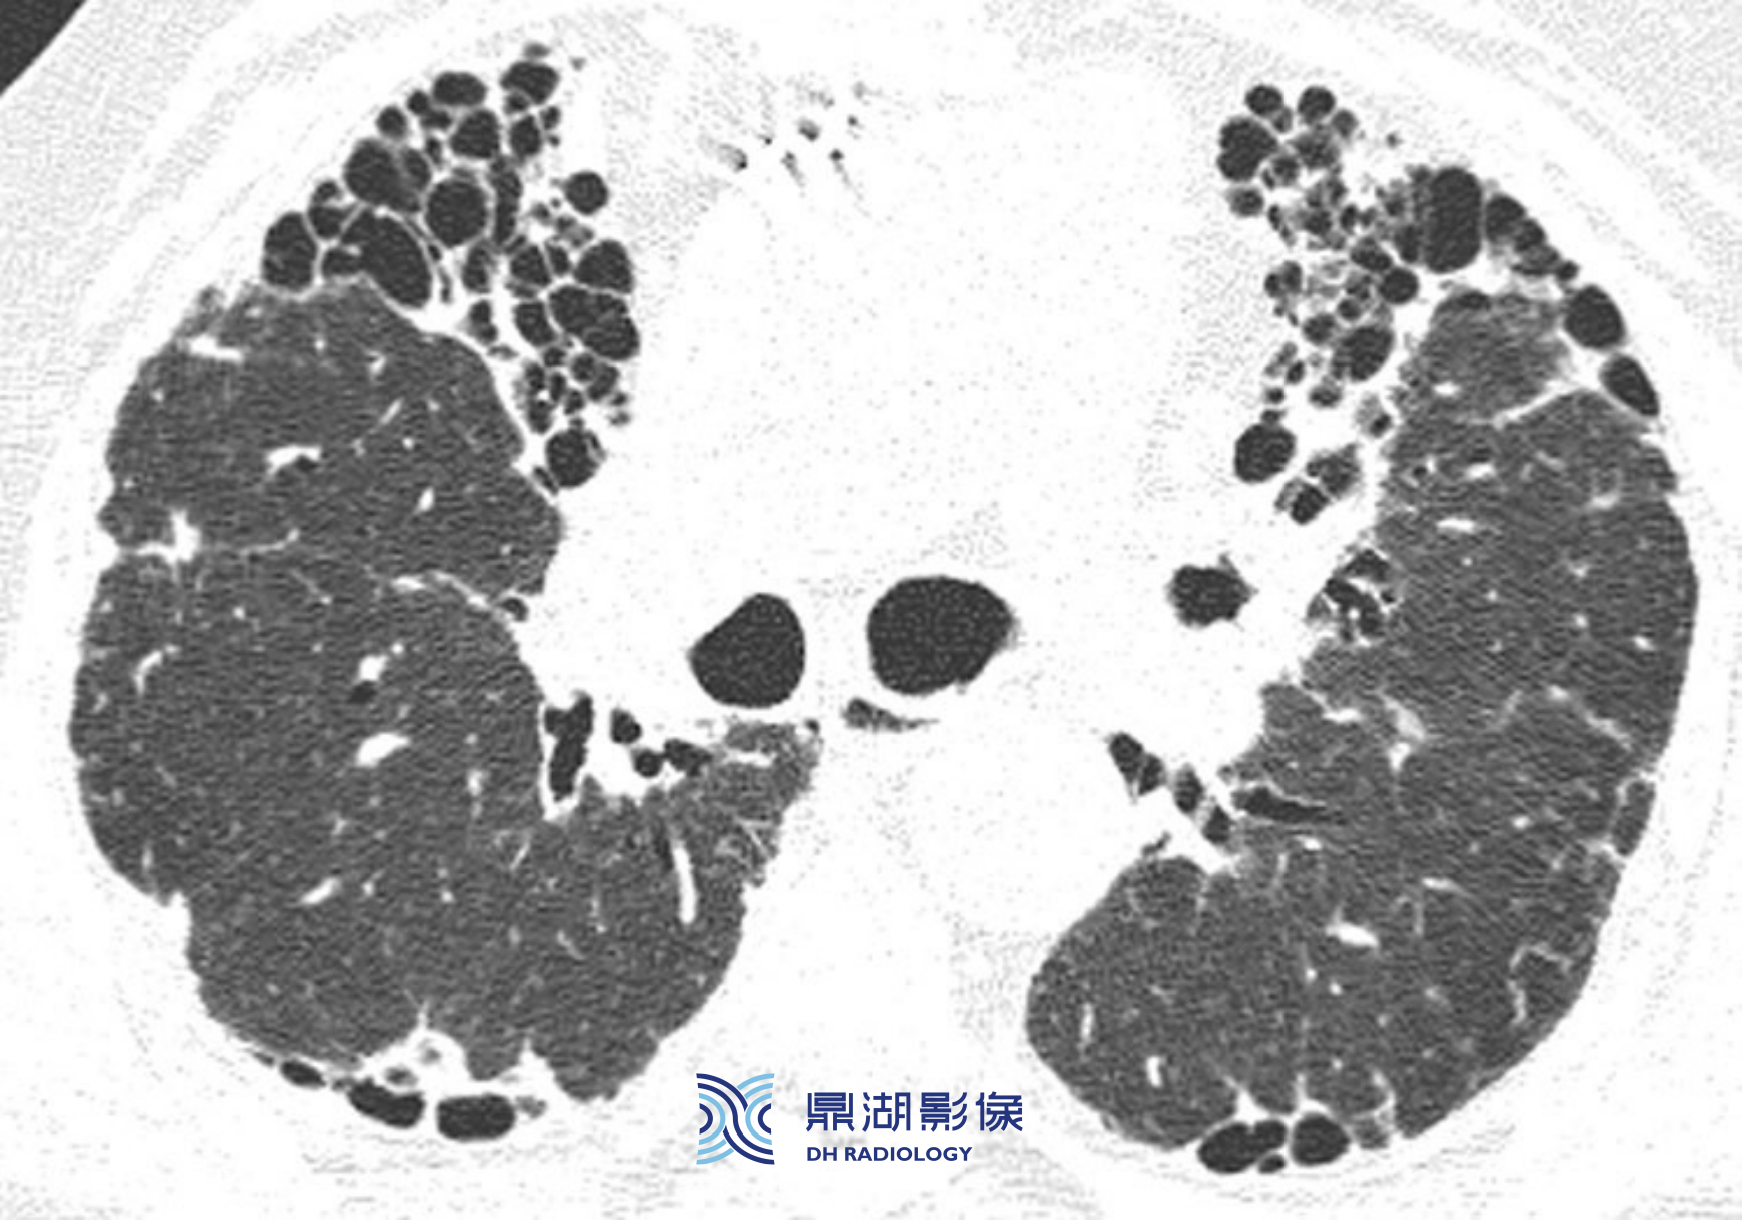

e7e783dec0c133d6d0659d8f8a9d13a1.png

结节病伴有类似随机分布的结节。粗略地看,结节呈随机分布且全肺受累。仔细观察可见结节呈散在不均匀分布,沿着叶间裂分布的结节(箭)数量多于随机分布的结节。

上述这种表现为淋巴分布结节加随机分布结节的模式,实际工作中更常见于肿瘤转移、癌性淋巴管炎,亚洲的结节病发病率要低于恶性肿瘤。